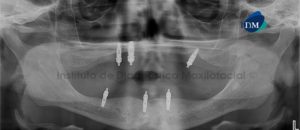

Paciente femenino de 64 años de edad, es referido al Instituto de Diagnóstico Maxilofacial para evaluación tomográfica de implantes dentales. A la evaluación de la